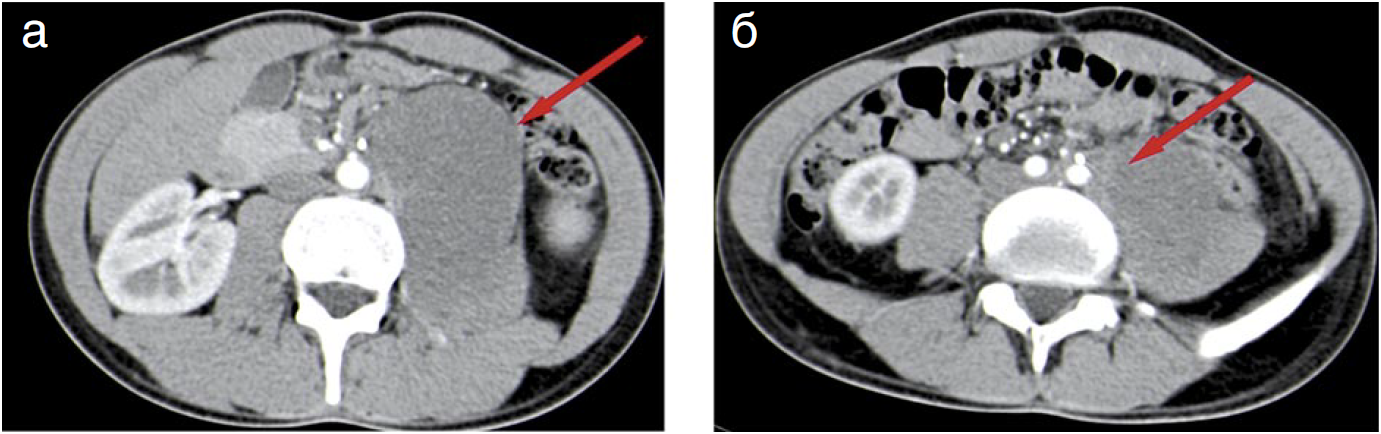

Через 9 мес после операции выявлен рецидив опухоли. Учитывая отсутствие жалоб и сдавления жизненно важных структур, рекомендовано наблюдение (рис. 2).

Рис. 2. Тот же пациент С. спустя 9 мес. КТ. Аксиальные срезы. Артериальная фаза. По ходу левой наружной подвздошной артерии (а) и в паховом канале (б) определяются рецидивные гиповаскулярные опухолевые узлы округлой формы с частично четкими контурами.

Fig. 2. Same patient S. after 9 months. CT. Arterial phase axial. Recurrent hypovascular tumor nodes round-shaped with partially sharp edges are observed along the left external iliac artery (a) and in the inguinal canal (b).

Через 9 мес после выявления рецидива отмечен рост опухоли, локализующийся в области левых подвздошных сосудов (рис. 3). По данным обследований размеры ранее выявленных рецидивных узлов (в паховом канале, толще брюшной стенки) увеличились с 2,5 до 3,5 см.

Рис. 3. Пациент C. через 9 мес после выявления 1-го рецидива (18 мес после операции). КТ. Аксиальные срезы. Артериальная фаза. По ходу левой наружной подвздошной артерии (а) и в паховом канале (б) определяются рецидивные гиповаскулярные опухолевые узлы округлой формы с частично четкими контурами, увеличенные в размерах по сравнению с предыдущим исследованием.

Fig. 3. Patient S. 9 months after the first relapse (18 months after the surgery). CT. Arterial phase axial. Recurrent hypovascular tumor nodes, round-shaped with partially sharp edges, enlarged in size compared to the previous study are observed along the left external iliac artery (a) and in the inguinal canal (b).